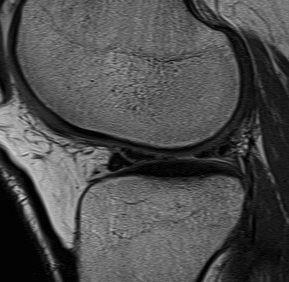

MRI Classification

Stoller 1987 J. Radiol.

Grade 0

- normal homogeneous low signal intensity

Grade I

- globular increase signal in meniscus

- doesn't reach either surface

Grade II

- linear increase signal, doesn't reach surface

- myxoid intra-meniscal degeneration / partially healed tear

Grade III

- increased signal intensity communicates with meniscal surface

- 70-90% accurate for true tear

- accuracy MM > LM